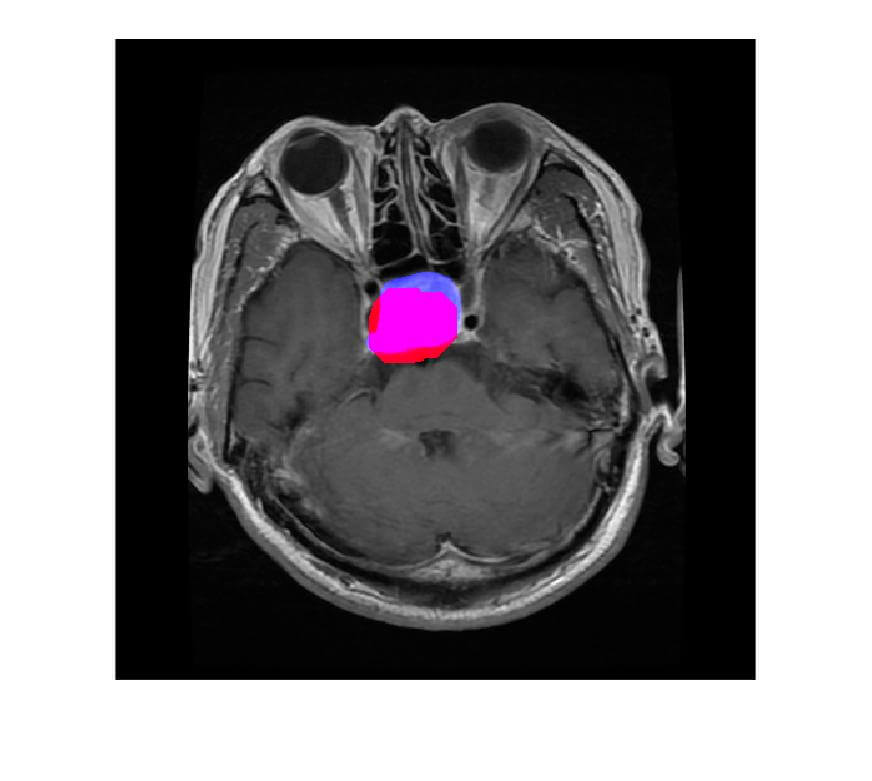

- The extracted tumor will be highlighted in red color and Blue color is the true tumor.